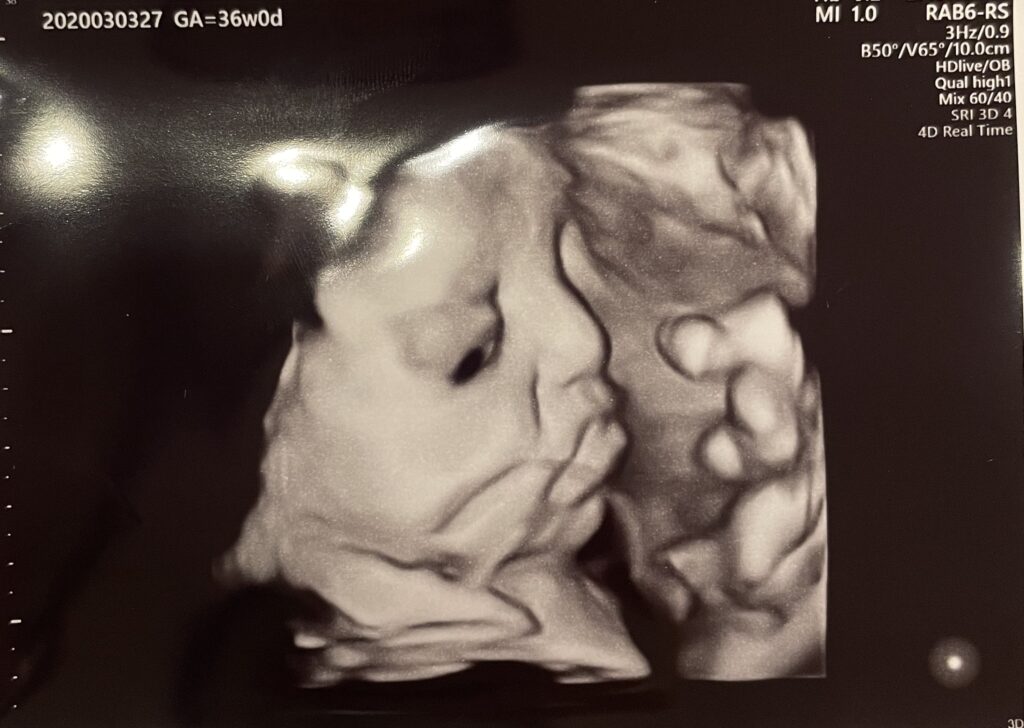

赤ちゃんの4Dエコー、だいぶリアルに感じられてきました。ほっぺもぷっくりしてきて、鼻も鼻の穴もしっかり見えます。臍の緒をちゅーちゅー吸って、母乳を飲む練習をしているみたいです😍

今更ですが育良クリニックの先生は、赤ちゃんのエコー写真を撮るのがすごく上手だと思います。

基本的に経腹エコーをするときはデフォルトで4Dエコーを撮るからなのか、いつもお顔をきれいにうつしてくれます。